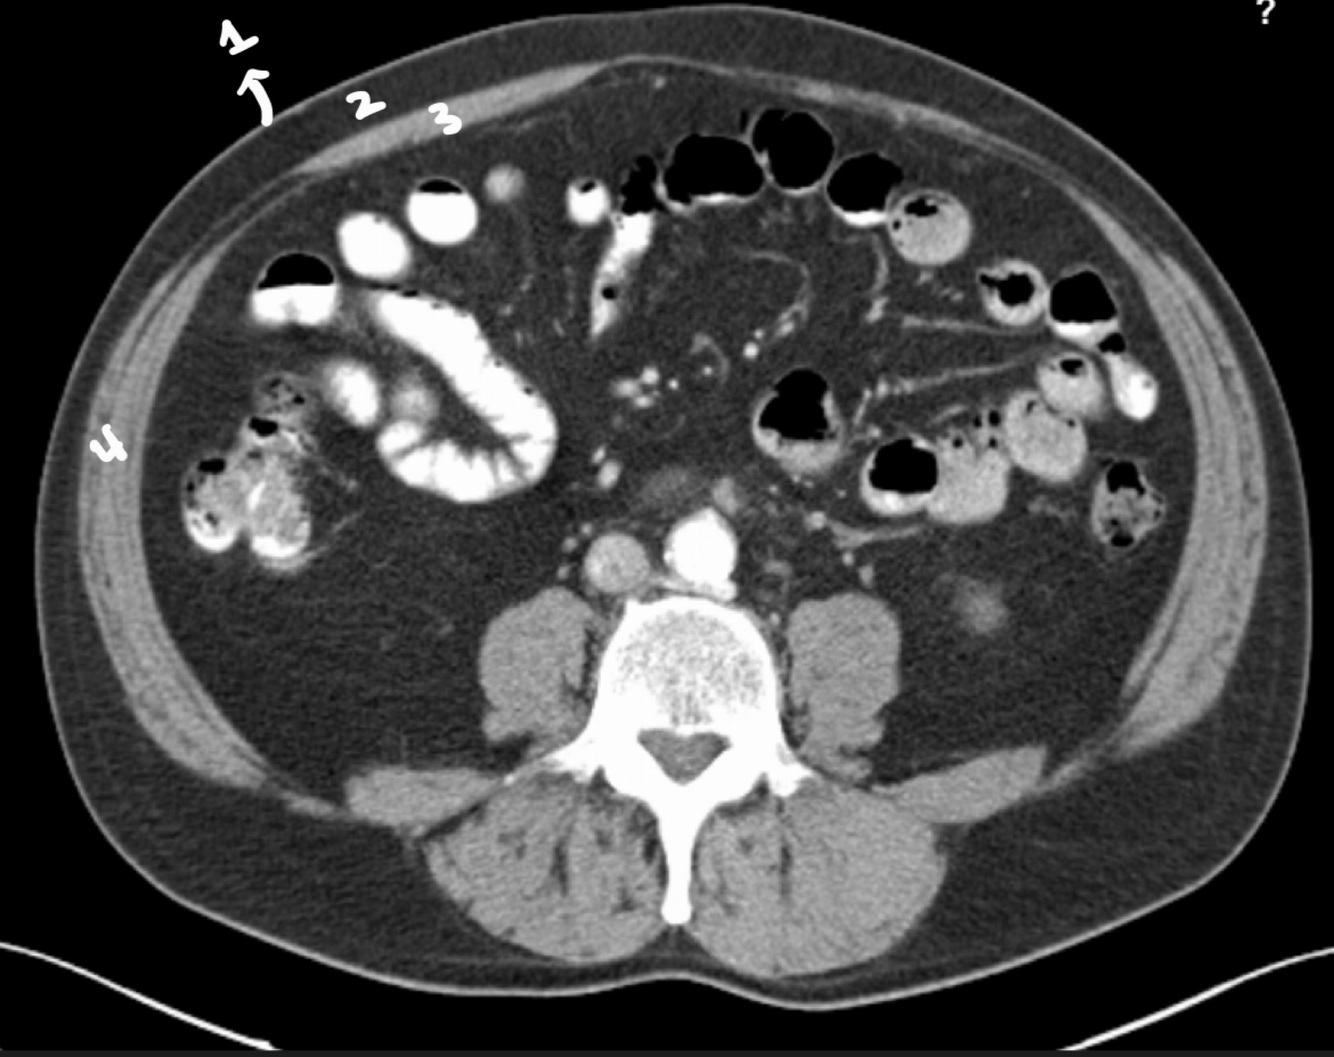

Name the marked structure

Ascending colon

1. Descending colon

2. Mesentery

Why are the loops hyperdense?

ORAL CONTRAST WITH IODINE has been applied